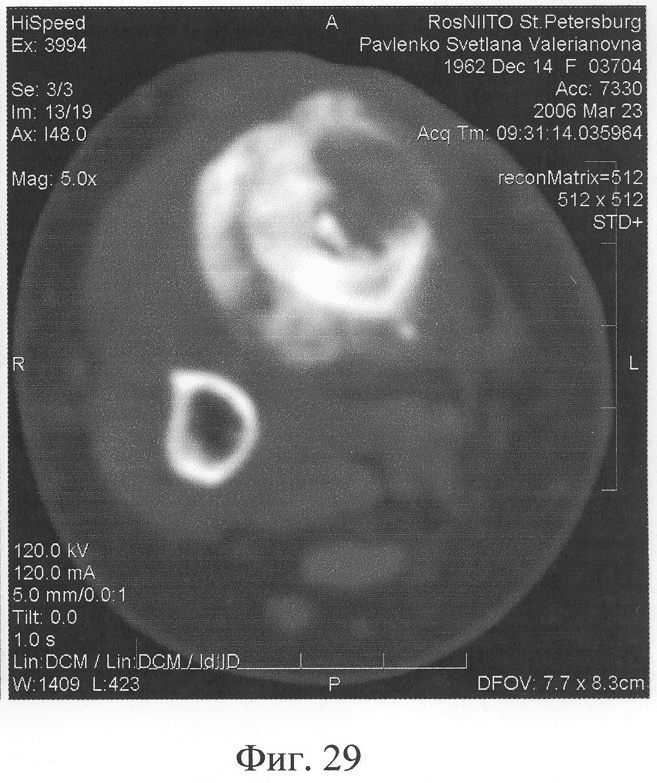

Аппарат внешней фиксации с левой голени демонтирован через 3 месяца после операции при клинико-рентгенологической картине сращения перелома. Аппарат внешней фиксации с правой голени демонтирован через 7 месяцев после операции при клинико-рентгенологической картине сращения перелома (фиг.20-25 – результат лечения). При рентгенологическом и томографическом контроле в трансплантатах отмечалось постепенное нарастание плотности костной ткани с формированием костной мозоли на всем протяжении между трансплантатом и костными фрагментами (фиг.26-29 – динамика данных компьютерной томографии правой голени: отмечается нарастание плотности костной ткани в области трансплантатов и формирование регенерата между смещенным трансплантатом и костными фрагментами; фиг.30-33 – динамика данных компьютерной томографии левой голени: отмечается нарастание плотности костной ткани в области трансплантатов и формирование регенерата между трансплантатом и костными фрагментами).